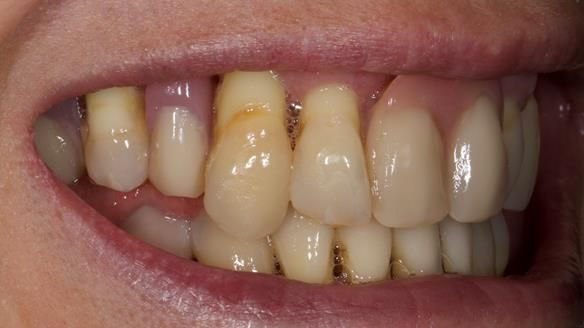

She had previously suffered from generalised periodontitis – stage IV, grade C, currently stable, with reduced attachment across the upper arch.

By the time she came to me, her periodontal condition was stable — but the aesthetics in the upper jaw were very poor.

- Her upper jaw had insufficient bone and would have required significant augmentation.

We provided her with an immediate upper denture (Mk 1), followed by a definitive metal-based upper denture (Mk 2). A lower removable partial denture was discussed, to be made only if needed once the upper treatment was complete. However, at review, this wasn’t necessary — Adnana had excellent neuromuscular control and function, even with a shortened dental arch (SDA).